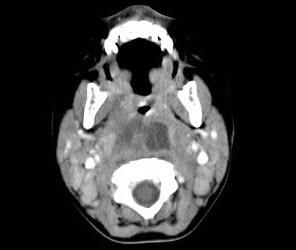

急性咽後壁膿腫多見於1~3歲嬰幼兒,成年人極少見,身體虛弱多病和營養不良的小兒最易患此病。臨床表現為發病急,初有畏寒、發熱、咽痛、不願吸乳、進食,日益加重;咽部因膿腫而共鳴腔縮小,說話含糊不清;咽部腫脹隆起使氣道變窄,故呼吸不暢;頭常偏向一側,頸部僵直,轉頭時肩部、軀幹一同轉向,藉以減輕咽痛和改善呼吸,進食時常嗆入鼻腔或吸入呼吸道引起劇烈咳嗽。